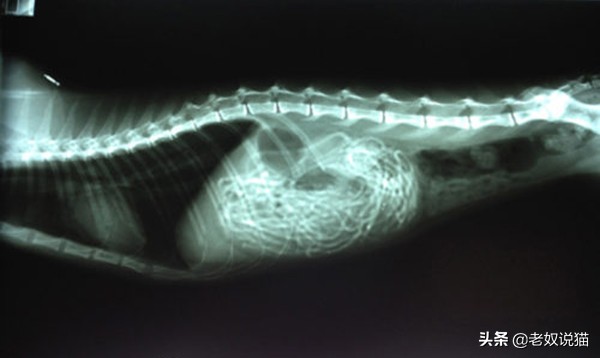

五、误食多根橡皮筋的猫

2岁的暹罗多根橡皮筋的猫